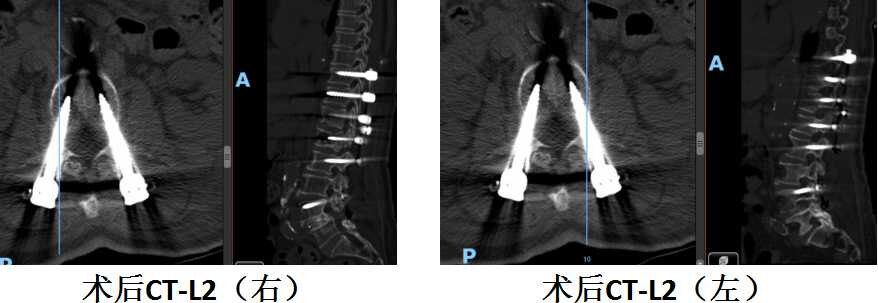

陈奶奶术后腰2水平螺钉位置良好

看这个MRI和CT的结果,T12和L1这两个地方的压缩性骨折肯定没跑了,但是这个骨折有一小部分压迫到了脊髓和神经,失去了打骨水泥这种微创手术的机会。不得不做了一个大的开放性的后路T12、L1椎体骨折切开复位内固定术。又给加了5对也就是10个钉子在里面。